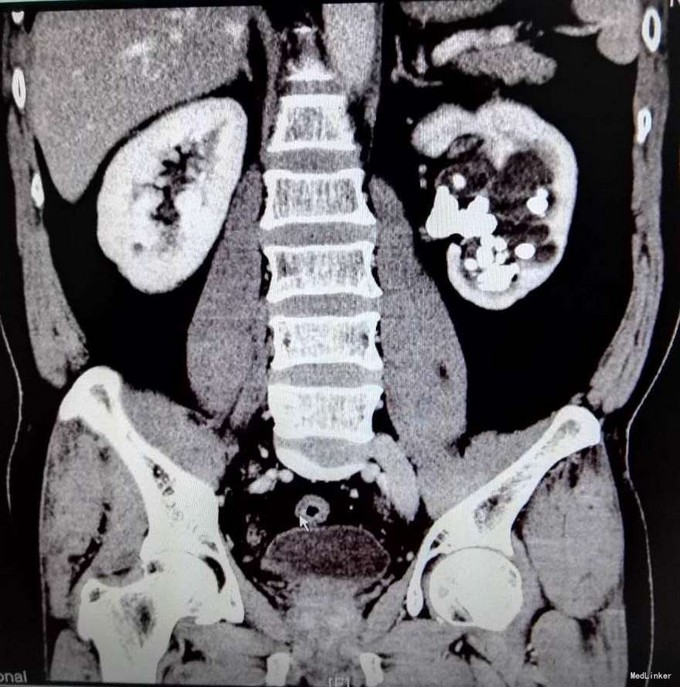

3、查体:未见明显阳性体征 4、辅助检查:外院平片:双肾多发结石;我院CTU:双肾多发结石,左侧肾盂输尿管连接处结石,并双肾积水,左肾明显,双侧肾盂、输尿管炎症。

5、诊断:肾结石(双肾多发结石) 6、治疗:入院后完善相关检查,双肾CTU:双肾多发结石,左侧肾盂输尿管连接处结石,并双肾积水,左肾明显,双侧肾盂、输尿管炎症。排除手术禁忌症后行左侧PCNL术,术后恢复良好,拔出肾造瘘管后,先出院休息,2周后返院进一步治疗